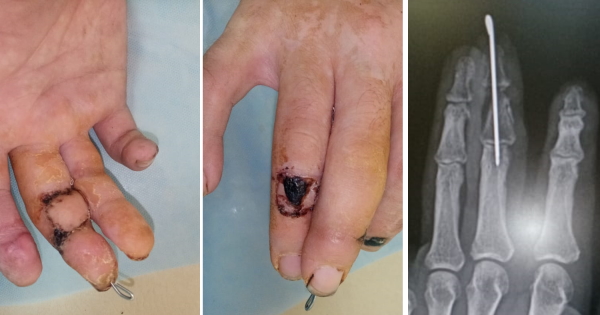

На 24 сутки пальцы разъединены, спица удалена. Начат активный курс ЛФК.

Планируется отсутствующую суставную поверхность средней фаланги преобразовать в ложный сустав, чтобы сохранить движения в ногтевой фаланге.

На момент описания этого случая, раны зажили, движения в суставах кисти в полном объеме, отсутствует только активное сгибание ногтевой фаланги III пальца, пассивные- в полном объеме.

Планируется через 3 месяца (после полной адаптации тканей) выполнить 2-х этапную пластику сухожилия глубокого сгибателя.